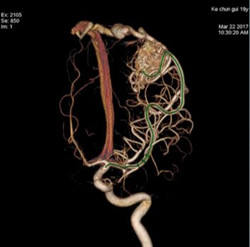

▲经过造影剂显影,脑血管变得清晰可见。

双侧颈内动脉3D重建技术,显示的是人两侧大脑半球动脉血管图像。